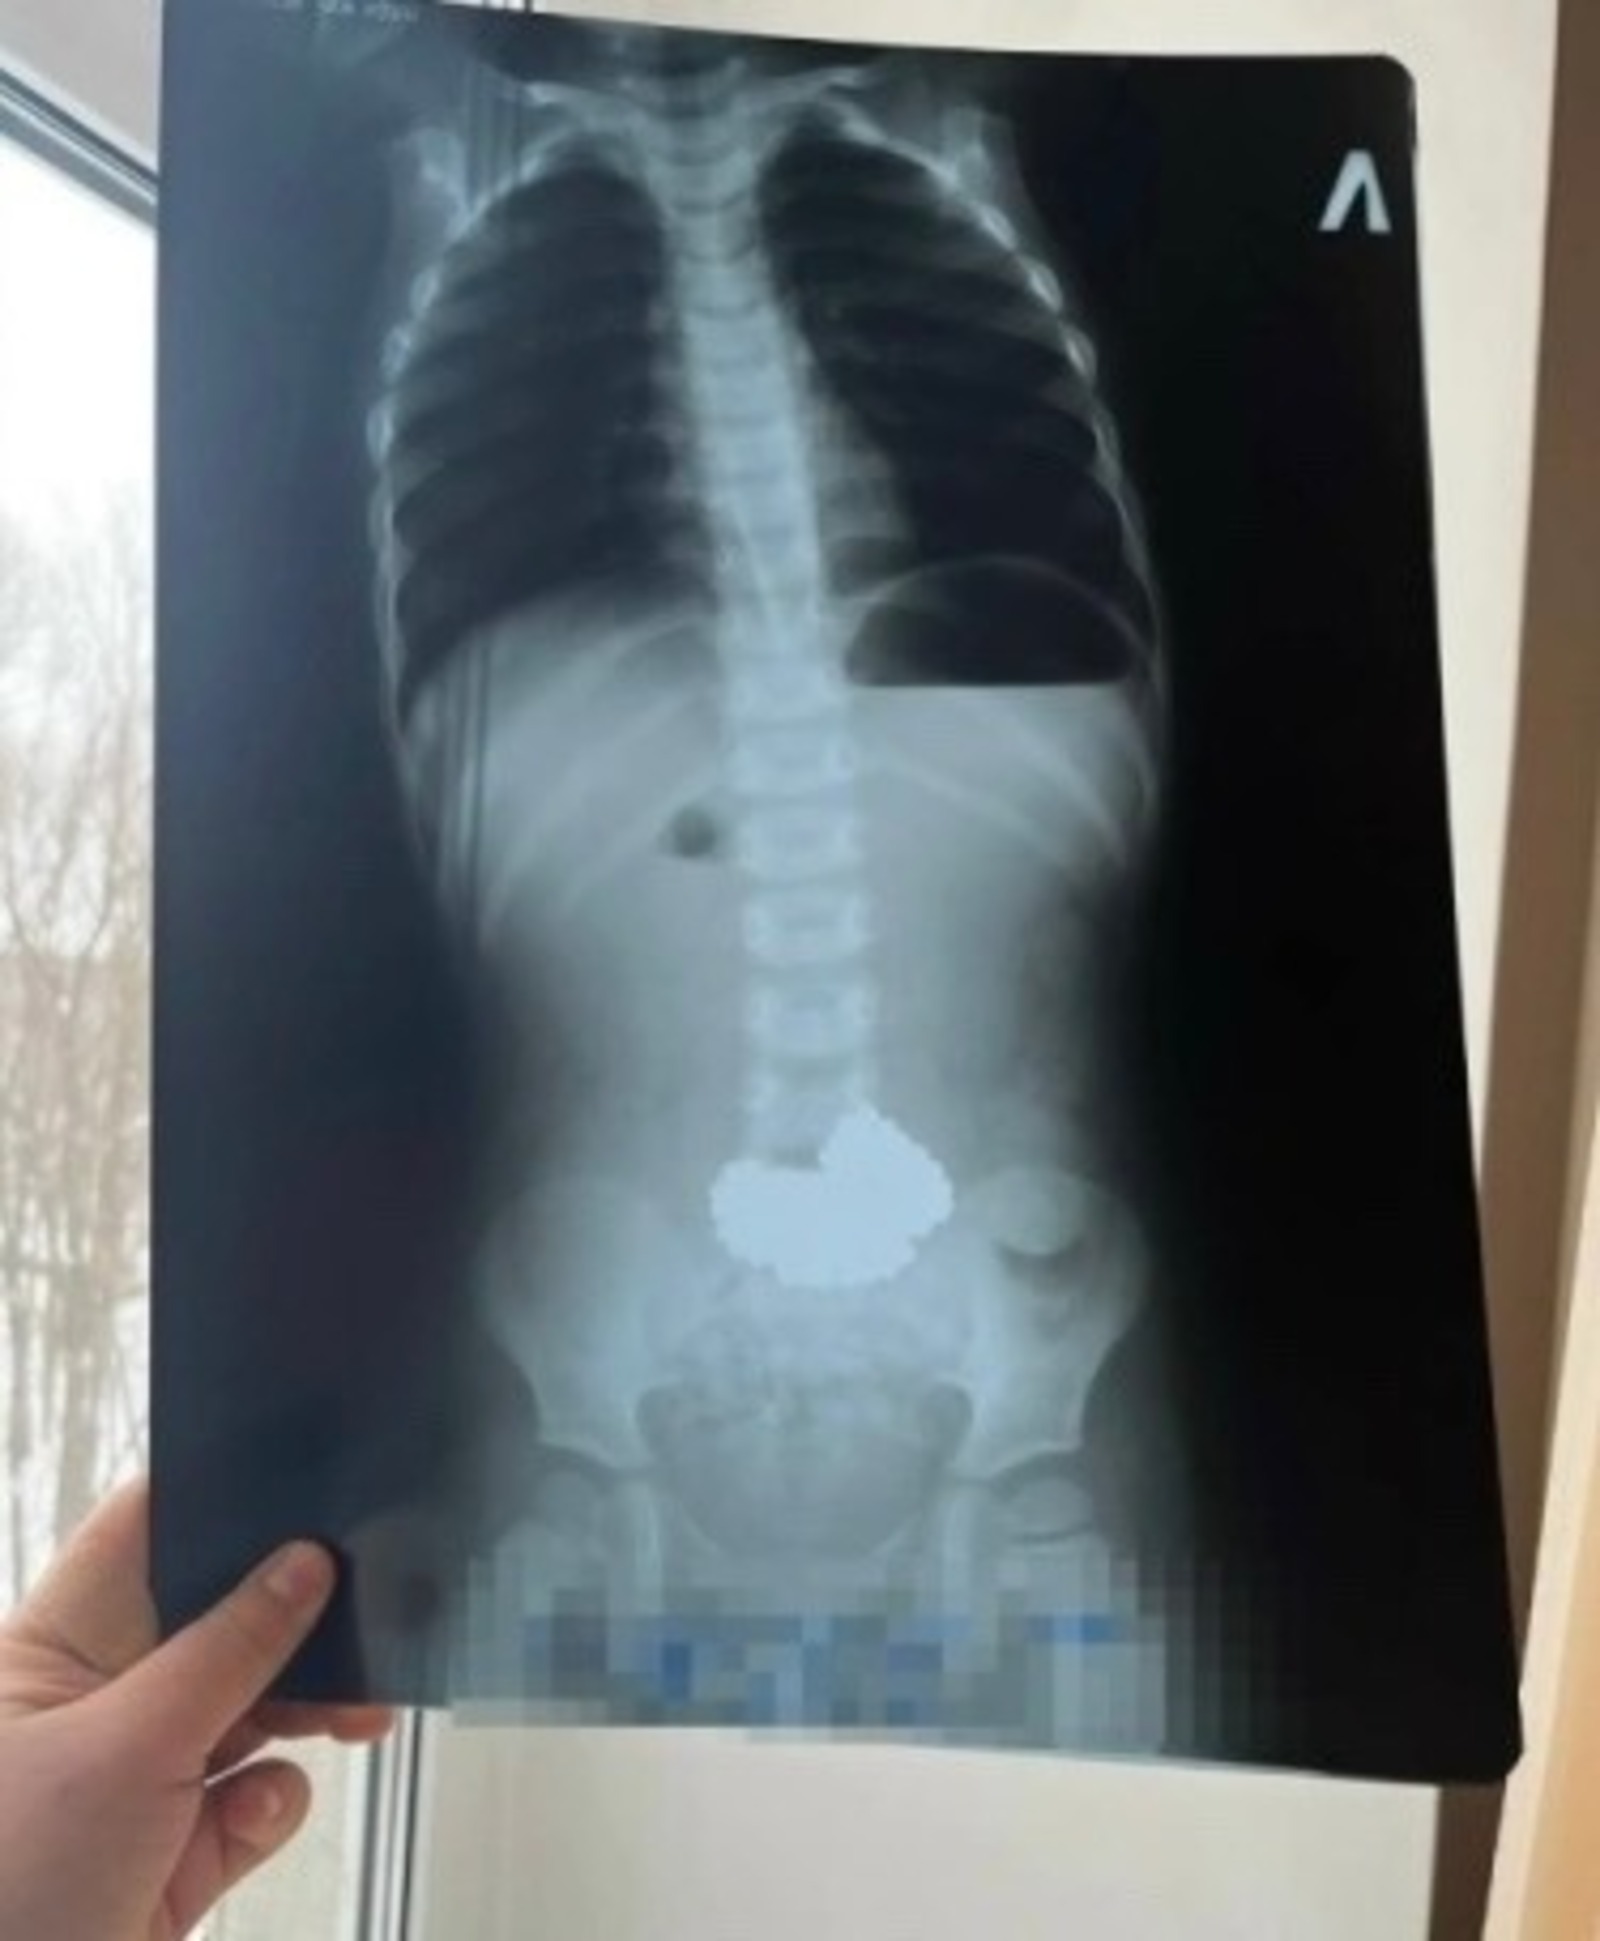

В Нефтекамске трехлетний ребенок проглотил 206 магнитных шариков, что привело к необходимости экстренной госпитализации и операции. Об этом сообщает ГБУЗ Башкирии города Нефтекамск.

Мальчика доставили в Республиканскую детскую клиническую больницу в Уфе, где врачи успешно удалили проглоченные неодимовые магниты. Ребенок находится вне опасности, однако произошедшее стало поводом для предупреждения родителей о рисках, связанных с магнитными игрушками.